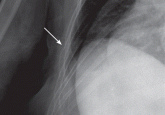

Salmonella-related mycotic pseudoaneurysm

A 74-year-old man is admitted to the hospital with a 7-day history of fever, rigors, chest pain, and general weakness. He underwent coronary...